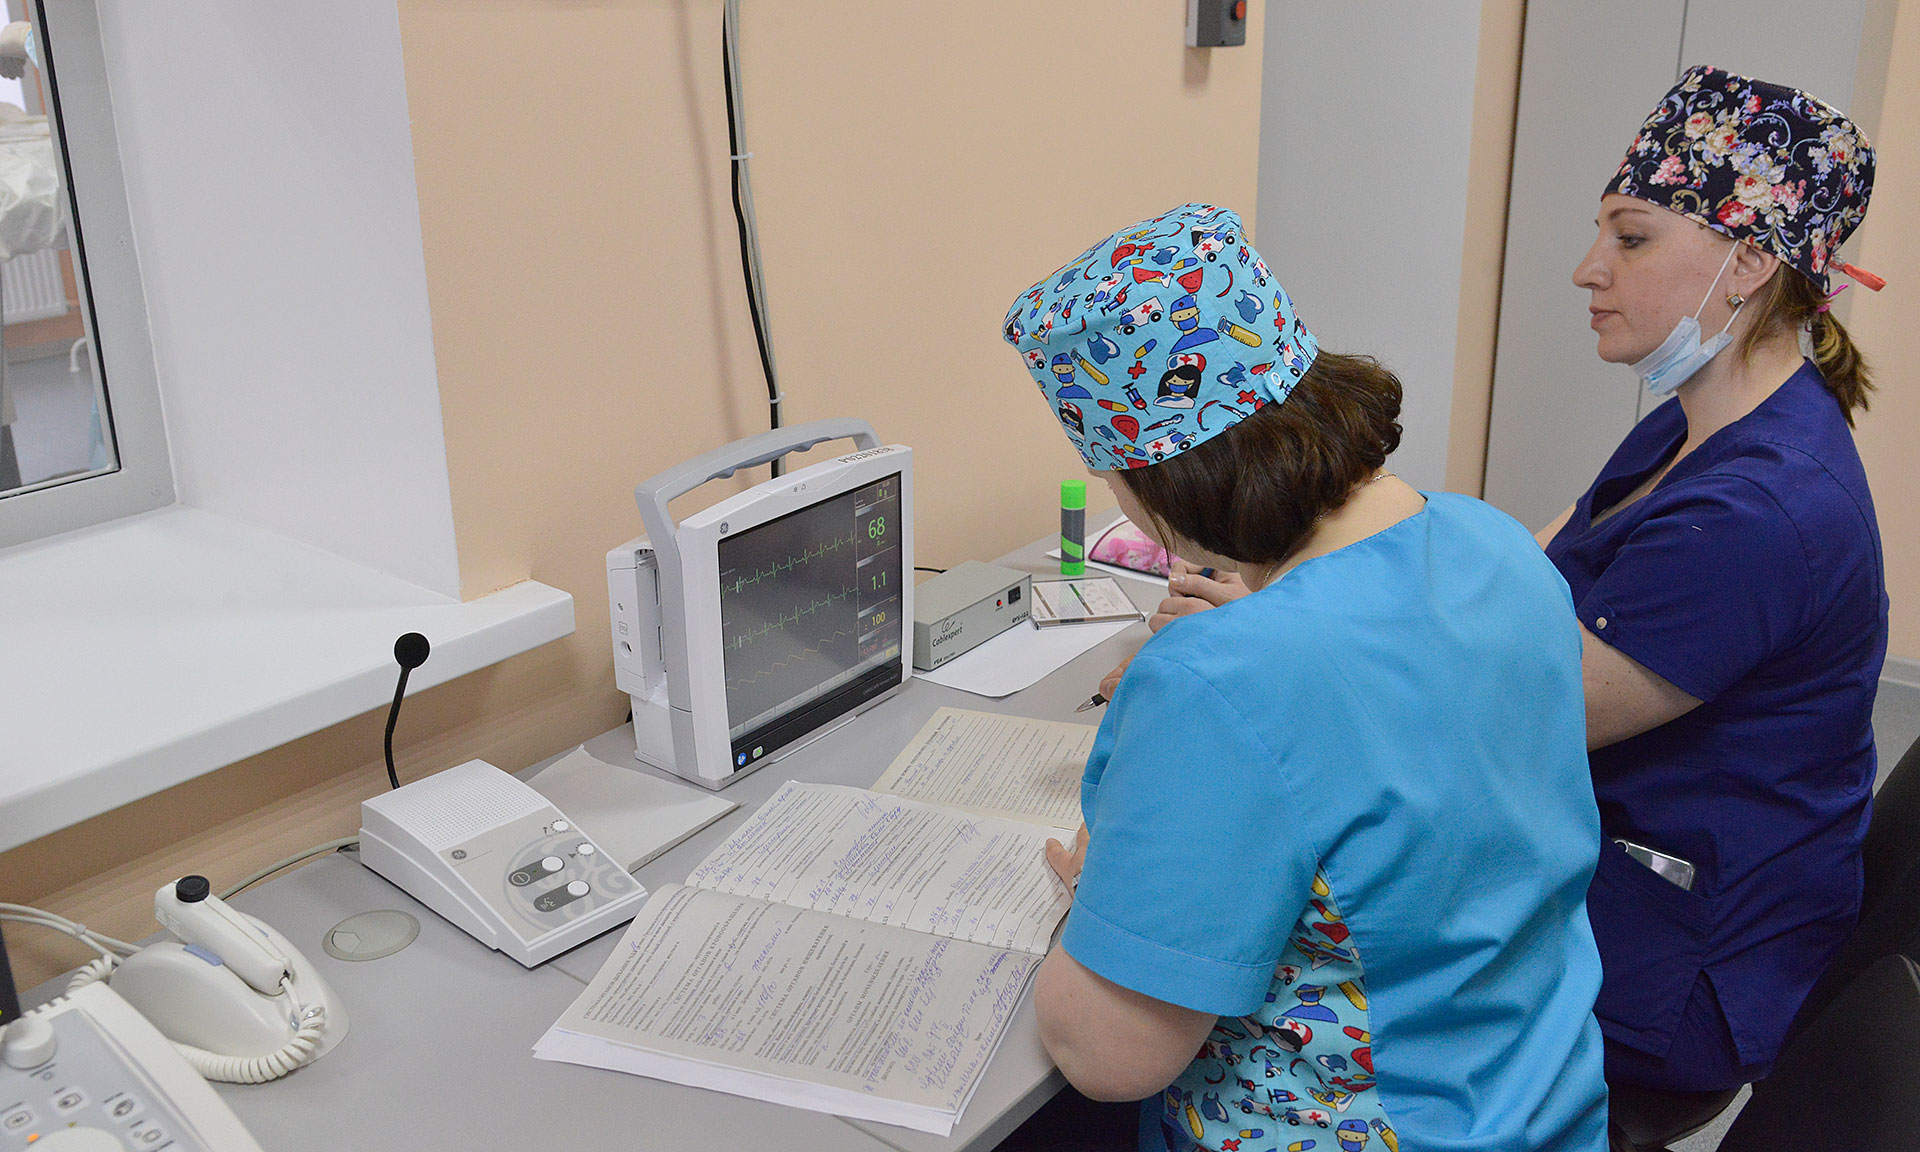

В отделении в настоящее время работают 4 высокопрофессиональных специалиста-врача по рентгенэндоваскулярным диагностике и лечению, которые прошли обучение на базах крупных федеральных клиник г. Москвы, г. Санкт-Петербурга и г. Курска.

В настоящее время в отделении проводится коронарография пациентам с сердечно-сосудистой патологией. В дальнейшем, при получении лицензии на проведение высокотехнологической медицинской помощи, будет проводиться стентирование сосудов.